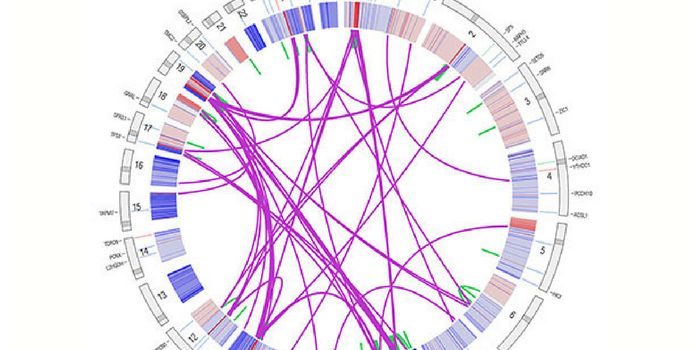

FEB 09, 2020MicrobiologyThe Pan-Cancer Analysis of Whole Genomes (PCAWG) has brought over 1,300 scientists together to gain new insights into th ...